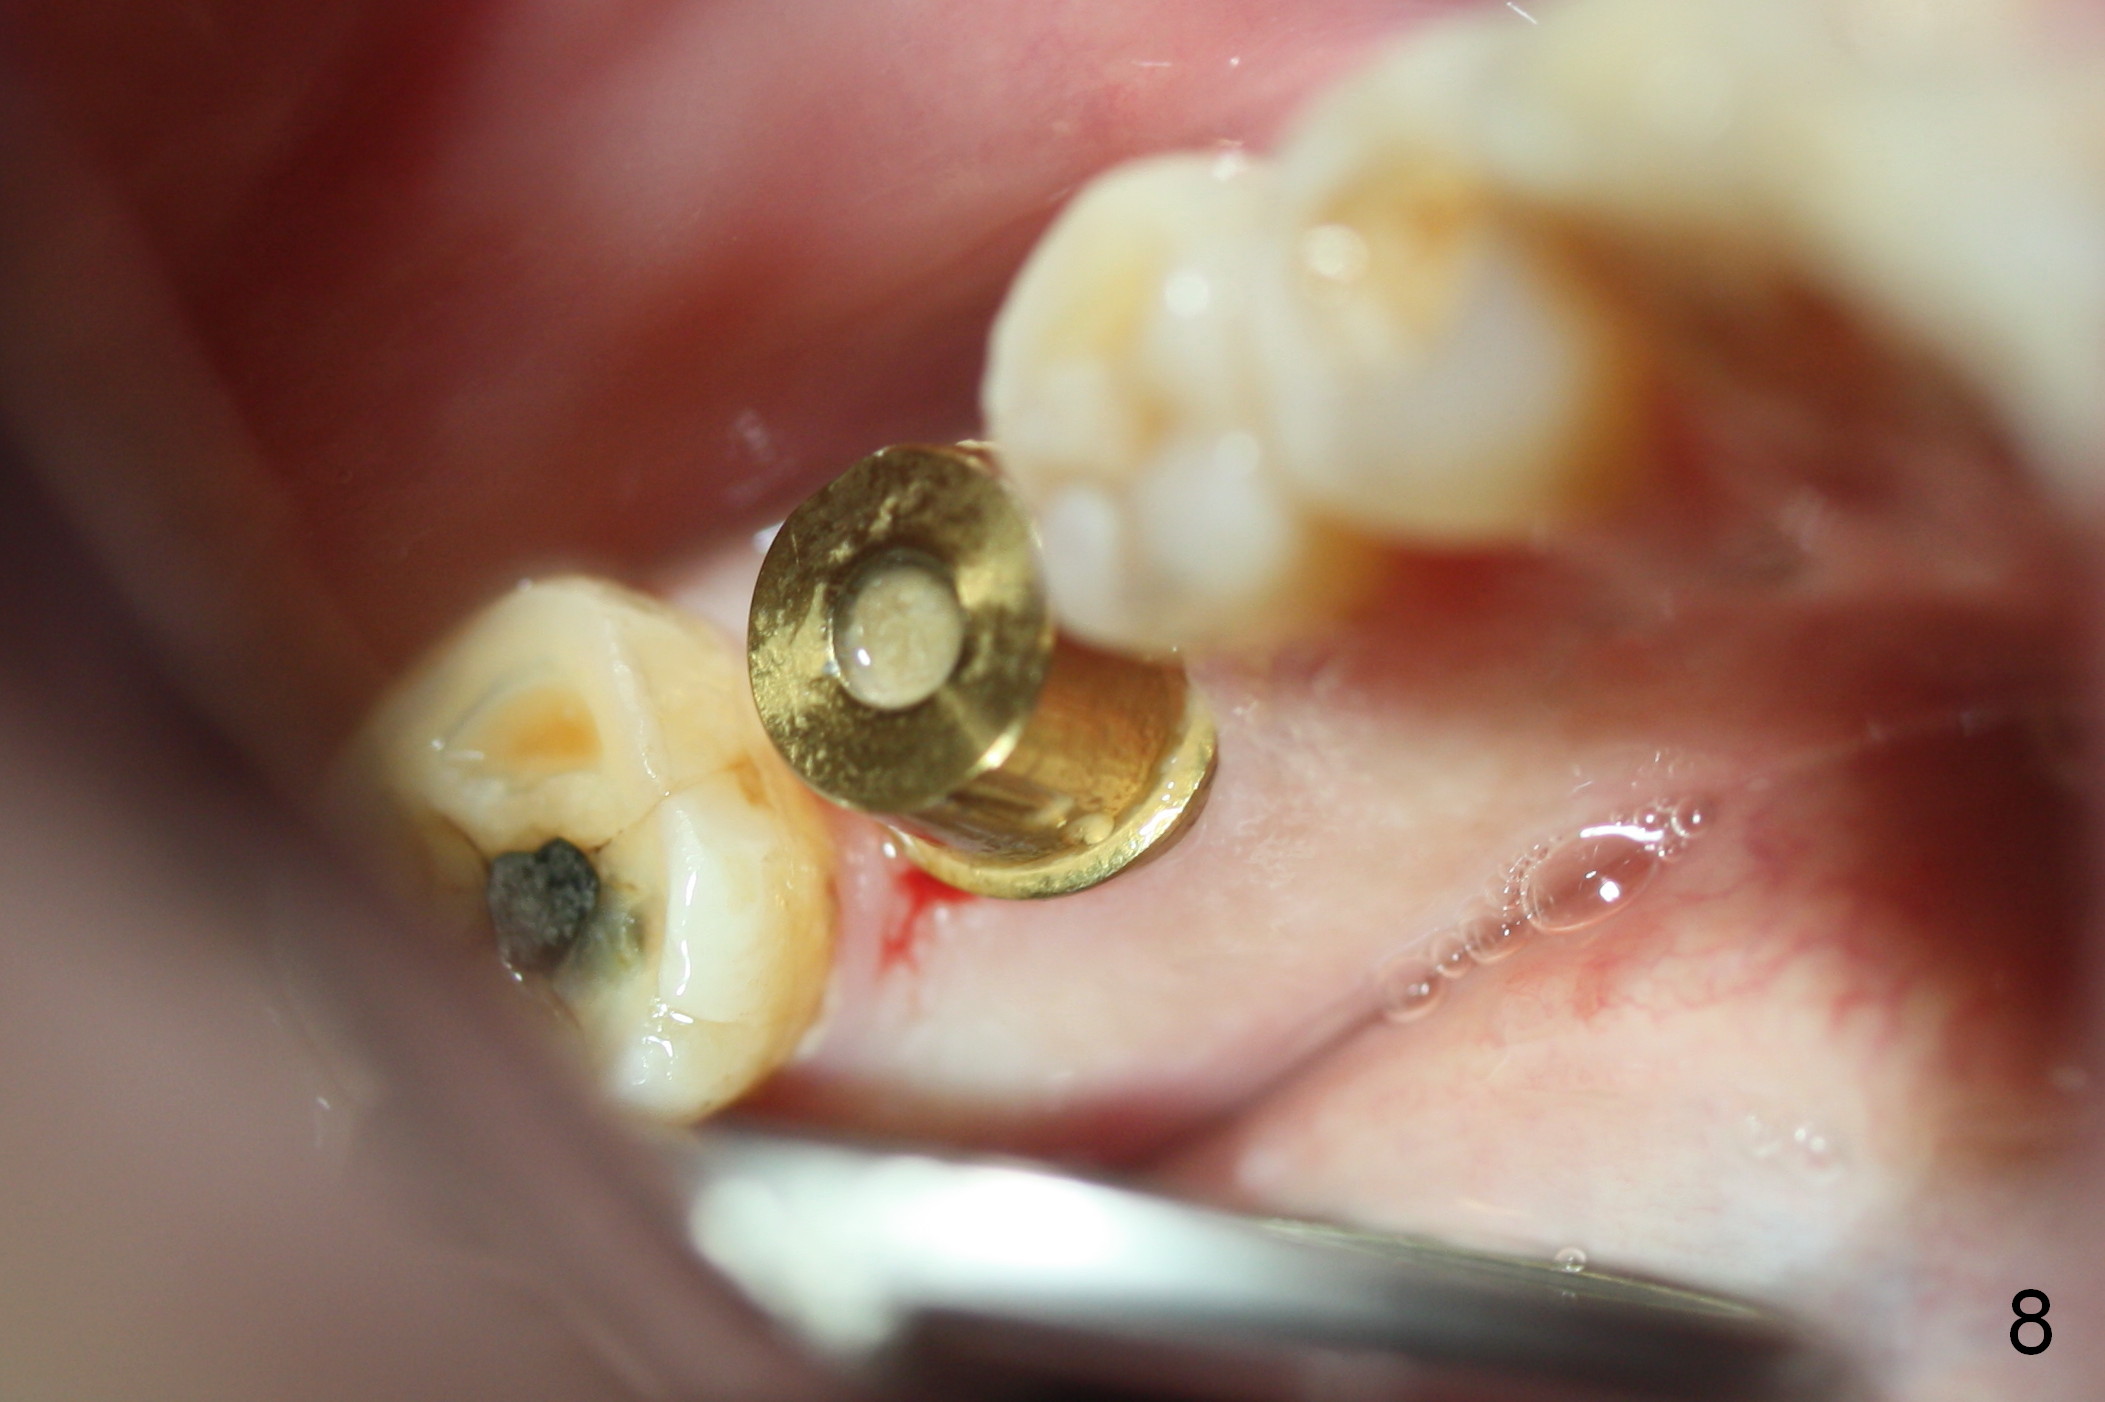

When the patient returns 1.5 months postop, the provisional has been fractured (Fig.8 lingual view). The abutment is loose. Intraop analysis of a PA shows existence of the peri-implant defect (Fig.7). When the abutment is removed, the implant is found to be stable. As a new smaller abutment (Fig.9: 6.8x4(3) mm) is being torqued at 35 Ncm, the abutment/implant does not turn. Impression for final restoration is taken. Postop analysis of PAs in Fig.6,7 shows that the peri-implant defect has been reduced in 1.5 months. Immediately postop, the fourth coronal large thread is buried in the solid bone, whereas 1.5 months postop the third thread appears inside the base bone.